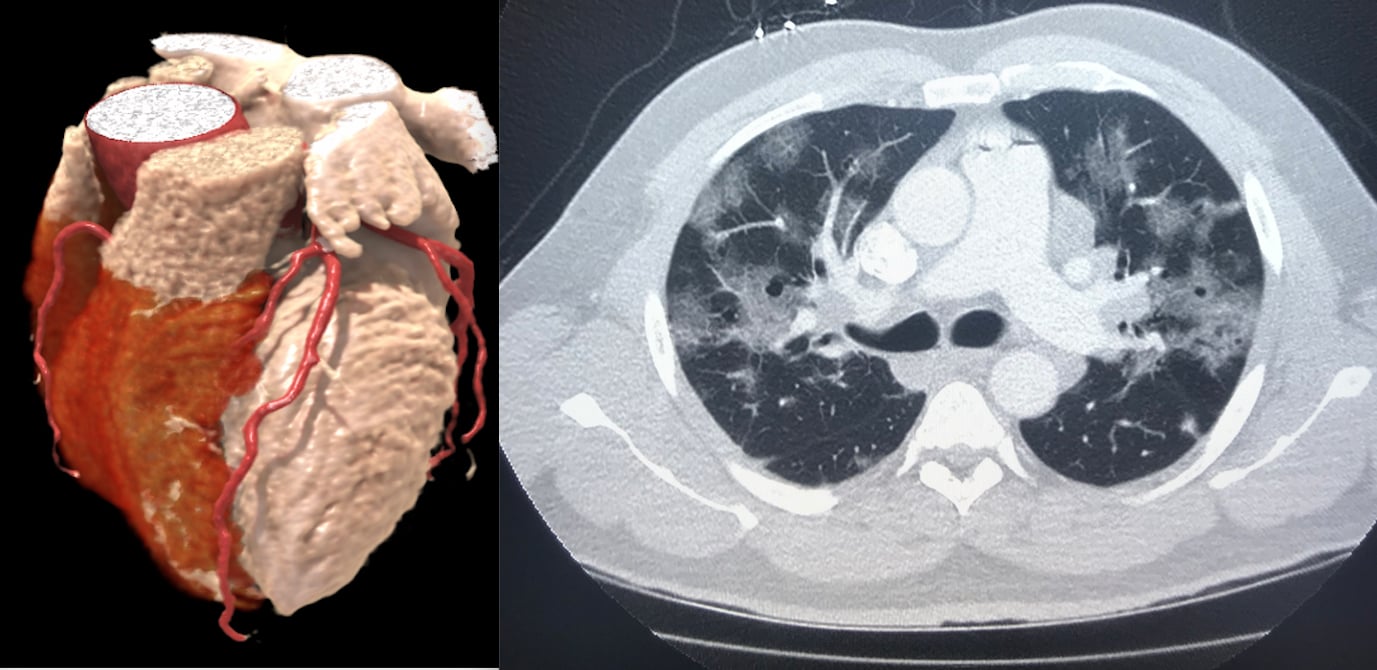

Left, a 3-D rendering of a heart from a cardiac CT exam. Right, a lung-CT exam showing the heart and ground glass lesions in the lungs of a COVID-19 patient. CT has become a front-line imaging modality in the COVID era because it offers both cardiac and lung information to help determine a patients disposition with chest pain, COVID-19 and COVID-caused myocarditis and pulmonary embolism.

Historically, CCTA has been used for triple rule out (TRO) of acute chest pain for the assessment of acute pulmonary embolism, acute coronary syndrome, and acute thoracic aortic dissection. However, during the COVID-19 crisis, the authors said they have added two more critical diagnoses, which include COVID lung infection and acute viral peri-myocarditis.

"We really found CT to emerge as as a front line test for the evaluation of chest pain for patients at intermediate risk, and now even more so in the COVID era with the issues of logistics in testing," Rose explained. "We find the ability to get patients in for a CT and out the door faster, with less contact is particularly well-suited to a COVID environment."

The study authors used a protocol that includes a gated non-contrast scan of the chest for the evaluation of COVID-19 lung disease and a coronary artery calcium score, followed by an ECG synchronized CTA of the heart, heart and aorta, or heart, pulmonary arteries, and aorta.

The authors said they found two positive acute peri-myocarditis cases using their CCTA protocol in 10 known COVID-positive patients. They also used a standard CT protocol that includes wide reconstructed field of view for the evaluation of the pulmonary parenchyma for the evaluation COVID lung disease in patients with cardiac symptoms and elucidating the etiology of atypical chest pain and dysrhythmia. The pulmonary findings have been interpreted in a standardized fashion, as laid out in recent guidance documents.[3]